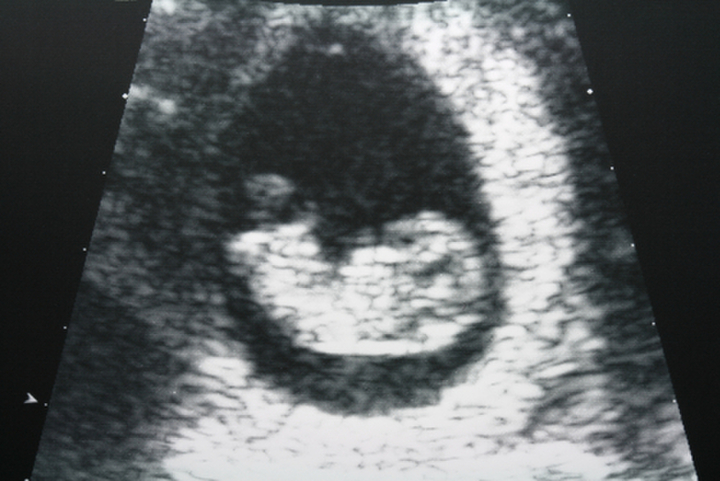

妊娠の週数は最終月経の開始日を妊娠0週0日と数え、生理が規則的にきている人であれば妊娠2週に排卵が起こり、妊娠3週に受精卵が着床したら妊娠成立となります。そのため、赤ちゃんがお腹の中に存在し始めるのは妊娠3週以降からとなります。一般的に妊娠初期は妊娠0~15週までを指すことが多いですが、最近では妊娠13週までを妊娠初期と定義することもあるようです。

一度流産を経験しているママであれば、さらに強く不安を感じてしまうことでしょう。特に出血や痛みといった自覚症状がないまま起こる稽留流産後のママにとっては、赤ちゃんを包んでいる袋の「胎のう」が確認できるか、次は心拍確認ができるかと、病院での健診のたびに不安に押しつぶされそうになるかもしれません。妊娠初期の流産は「予防や治療ができない、ある一定の割合で起こってしまう自然現象」と頭ではわかっていても、気持ちが追いつかないことのほうが多いです。